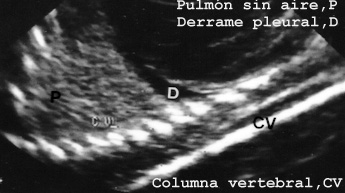

Por el contrario el aspecto de un pulmón sin aire porque no ha respirado, es característico y se diferencia tanto del que le ha entrado aire como de la atelectasia adquirida. Esto hace que la ecografia postmortem pueda ser utilizada de diagnostico rápido en la sala de autopsia en caso de estudios forenses para determinar si un niño ha muerto dentro del útero o si ha nacido vivo y ha respirado. En nuestra experiencia en todos los casos hemos diagnosticado correctamente cuando el neonato había respirado o no (Fig. 49B)